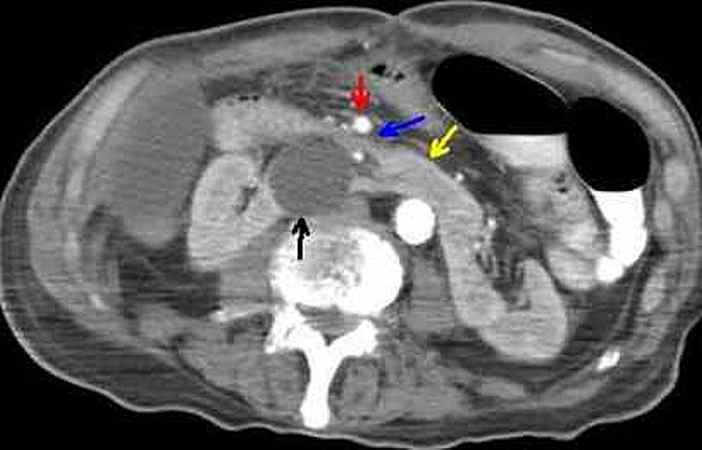

A misdiagnosed cause of early postoperative bowel obstruction.

In the setting of altered anatomy, diagnosis of superior mesenteric artery syndrome requires high clinical and imaging suspicion as the defined imaging criteria cannot be applied.